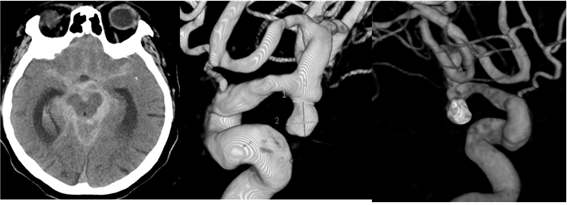

뇌동맥류는 다음과 같은 검사를 통해 진단합니다.

- 뇌 컴퓨터단층촬영(CT): 뇌출혈 여부를 신속하게 확인할 수 있습니다.

- 자기공명영상(MRI): 뇌의 상세한 영상을 제공하여 동맥류의 위치와 크기를 파악하는 데 도움이 됩니다.

- 뇌혈관 조영술: 혈관 내에 조영제를 주입하여 X선 촬영을 통해 동맥류의 정확한 모양과 위치를 확인합니다.

이러한 검사를 통해 뇌동맥류의 존재 여부와 특성을 파악하여 적절한 치료 계획을 수립합니다.